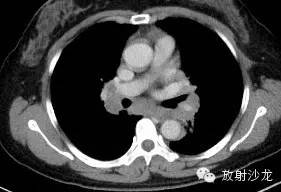

第一例:

44岁女性,因左乳腺结节行胸部CT检查发现胸部病变。

三幅图为典型的胸部结节病表现,肺门纵隔多发淋巴结肿大,各淋巴结不融合、不坏死、不侵犯邻近结构。右侧气管旁、右侧肺门、左侧肺门、主肺动脉窗淋巴结肿大,为1,2,3,4淋巴结。

双肺底见间质性病变。

CT拟诊结节病,呼吸内科建议定期观察。未经任何治疗11个月后复查示肺门纵隔淋巴结正常,双肺底间质性病变消失。左乳腺结节无变化(图略)